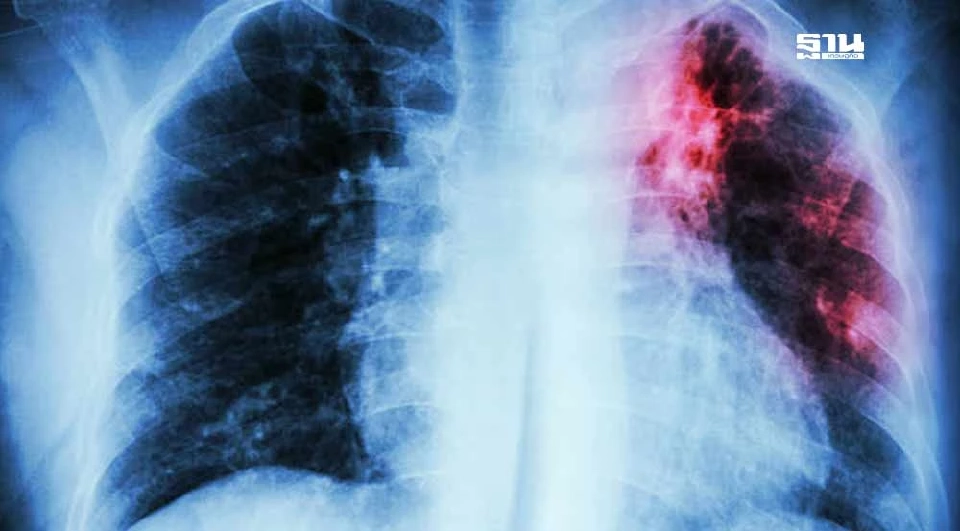

รู้หรือไม่ สูบบุหรี่ทำให้ปอดอ่อนแอ ลดภูมิคุ้มกัน เพิ่มความเสี่ยงในการติดเชื้อวัณโรคและทำให้โรคกำเริบหลังการรักษา

การสูบบุหรี่เพิ่มความเสี่ยงการติดเชื้อวัณโรค (TB) และยังเป็นสาเหตุสำคัญที่ทำให้วัณโรคที่อยู่ในระยะสงบกลับมาเป็นใหม่ได้ รวมถึงทำให้โรคมีความรุนแรงมากขึ้น

โดยมีผลต่อการฟื้นฟูและรักษาโรคได้ยากขึ้น ส่งผลให้ความเสี่ยงในการเสียชีวิตเพิ่มสูงขึ้นหลายเท่า การสูบบุหรี่ทำให้ภูมิคุ้มกันของร่างกายลดลง ส่งผลให้ปอดไม่สามารถกำจัดเชื้อวัณโรคที่หายใจเข้าสู่ปอดได้ดีเท่าคนที่ไม่สูบบุหรี่ การสูบบุหรี่จึงทำให้การรักษาวัณโรคไม่ประสบผลสำเร็จ และเพิ่มความเสี่ยงในการดื้อยา

การสูบบุหรี่ทำให้เกิดการอักเสบในปอดและทำลายเนื้อเยื่อปอดอย่างเรื้อรัง ส่งผลให้โครงสร้างของปอดเสียหายและระบบภูมิคุ้มกันลดประสิทธิภาพลง เมื่อปอดไม่สามารถกำจัดเชื้อวัณโรคได้อย่างมีประสิทธิภาพ เชื้อวัณโรคที่หายใจเข้าสู่ปอดก็จะเจริญเติบโตและแพร่กระจายได้ง่ายขึ้น

ผู้ที่สูบบุหรี่ยังมีโอกาสสูงที่วัณโรคจะกลับมารุนแรงหรือลุกลามแม้จะผ่านการรักษาแล้ว ด้วยการที่ภูมิต้านทานลดลงจากการสูบบุหรี่ทำให้ปอดไม่มีความสามารถในการต่อต้านเชื้อวัณโรคได้อย่างมีประสิทธิภาพ

การสูบบุหรี่ยังส่งผลกระทบต่อการทำงานของระบบทางเดินหายใจ โดยทำให้การทำงานของปอดเสื่อมสภาพ และเพิ่มความเสี่ยงในการติดเชื้อจากภายนอก นอกจากวัณโรคแล้ว ยังเสี่ยงต่อโรคอื่น ๆ เช่น มะเร็งปอด, โรคปอดอุดกั้นเรื้อรัง (COPD), และปัญหาทางเดินหายใจต่าง ๆ การสูบบุหรี่ทำให้เยื่อบุทางเดินหายใจเสื่อมสภาพและไม่สามารถกำจัดสารพิษได้อย่างเต็มที่ ส่งผลให้ภูมิต้านทานลดลง รวมถึงความสามารถในการฟื้นตัวจากโรคต่าง ๆ เช่น วัณโรคก็ลดลงไปด้วย